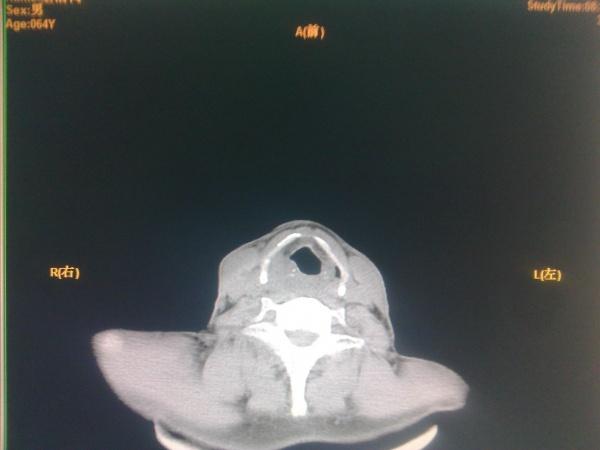

声门上区及声门区结构对称,双侧声带未见明显增厚,双侧梨状窝及喉咽腔

图片尺寸497x497